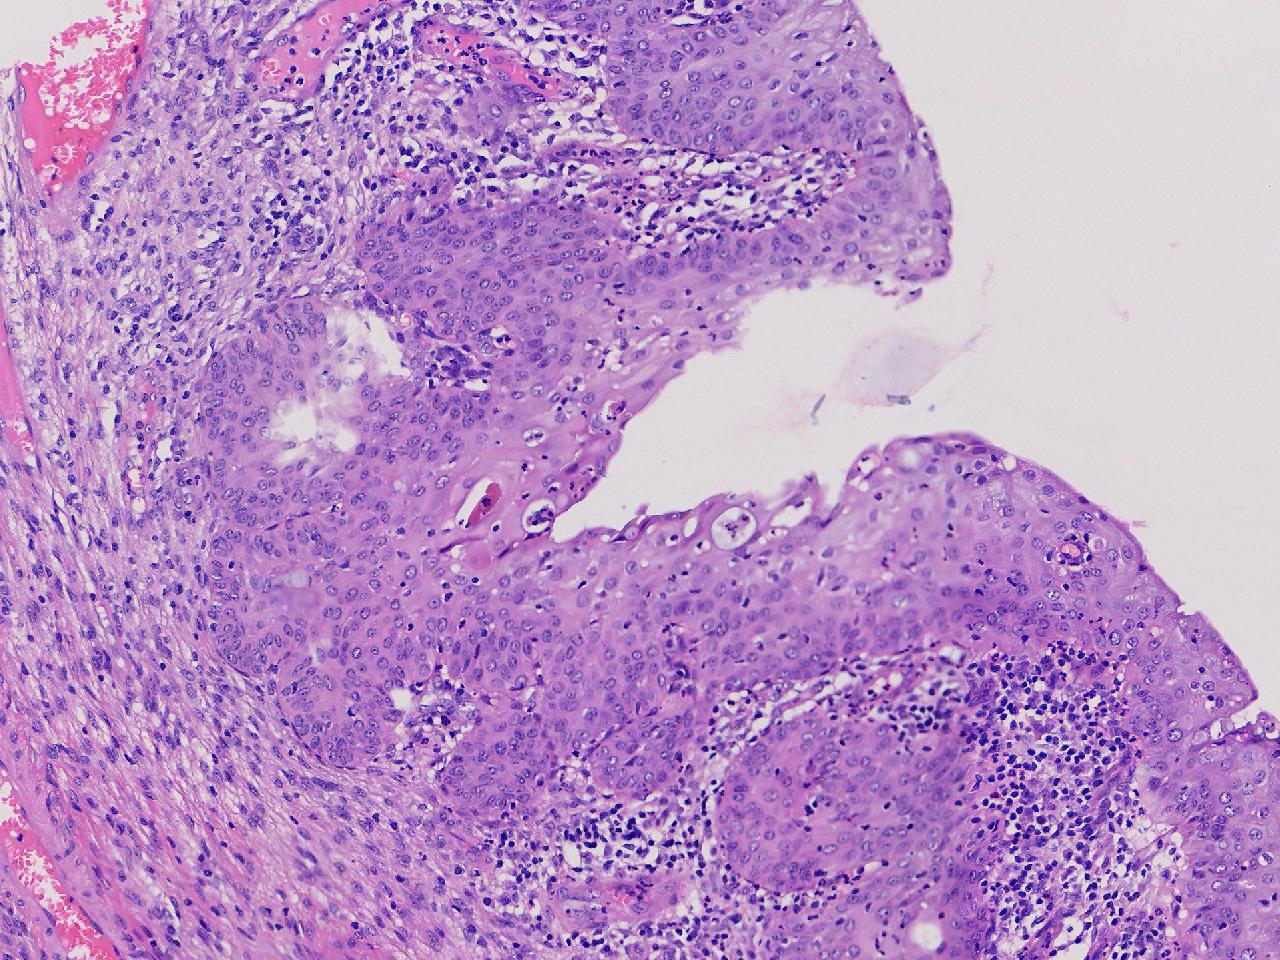

炎? 低级别?

性别年龄42岁临床诊断宫颈赘生物

一般病史女,42岁,妇检时发现宫颈赘生物,大小0.2cmx0.5cm

炎症

低级别诊断需要有个尺子,这个尺子就是“似是而非为非”,这个连似是而非都达不到。

有非典型鳞化,建议HPV检测

慢性宫颈炎伴腺上皮鳞化。